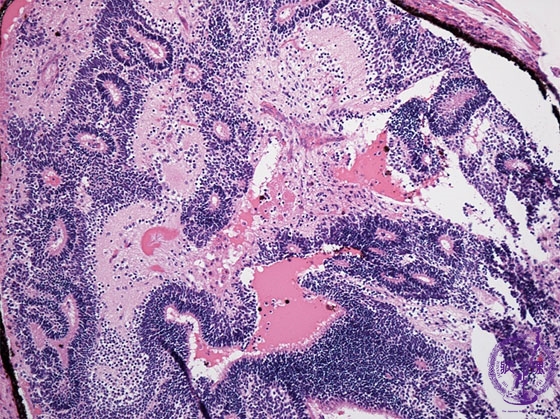

未熟奇形腫ミクロ像(HE中拡大)

ミクロ像(HE中拡大):未熟奇形腫。未熟な神経外胚葉組織が認められる。